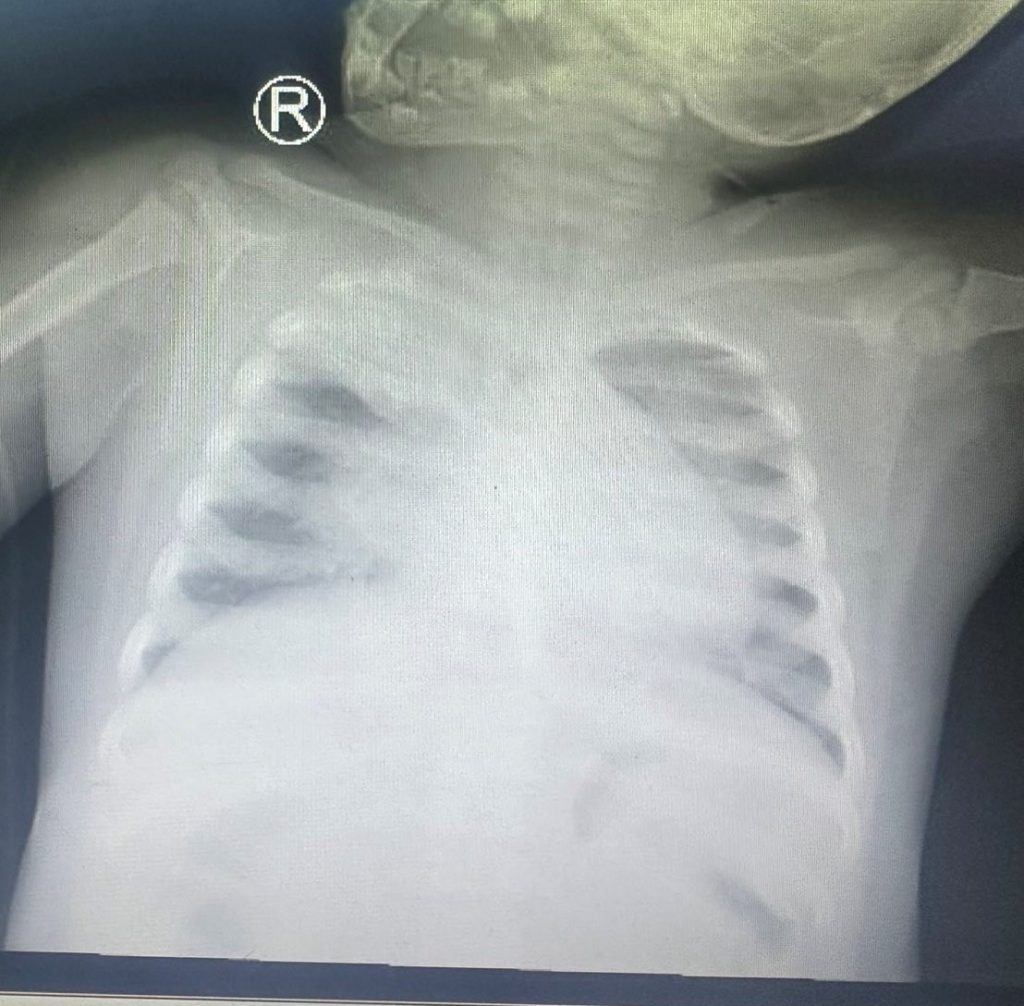

Tình trạng lúc nhập viện, trẻ li bì tím tái, SpO2 80-82% với thông số máy thở cao (chế độ kiểm soát áp lực tần số 30 lần/phút, IP 24 cmH2O, PEEP 14 cmH2O, FiO2 80%, khí máu động mạch cho thây tình trạng thiếu oxy máu nặng, chỉ số oxy hóa máu OI: 32, biểu hiện hội chứng suy hô hấp cấp tiến triển nặng (ARDS acute respiratory distress syndrome), Xquang phổi: tổn thương lan tỏa 2 bên phổi, xẹp đỉnh phổi (P). Chẩn đoán: Viêm phổi nặng – ARDS nặng do cúm A/H1 pdm 2009.